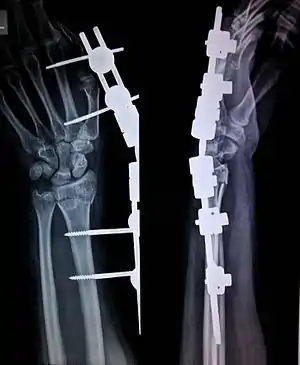

External fixation

External fixation is a surgical treatment wherein rods are screwed into bone and exit the body to be attached to a stabilizing structure on the outside of the body. It is an alternative to internal fixation, where the components used to provide stability are positioned entirely within the patient's body. It is used to stabilize bone and soft tissues at a distance from the operative or injury focus. They provide unobstructed access to the relevant skeletal and soft tissue structures for their initial assessment and also for secondary interventions needed to restore bony continuity and a functional soft tissue cover.

In this kind of reduction, holes are drilled into uninjured areas of bones around the fracture and special bolts or wires are screwed into the holes. Outside the body, a rod or a curved piece of metal with special ball-and-socket joints joins the bolts to make a rigid support. The fracture can be set in the proper anatomical configuration by adjusting the ball-and-socket joints. Since the bolts pierce the skin, proper cleaning to prevent infection at the site of surgery must be performed.

The parts of an external fixator include:

- Schanz pin

- Connecting rods

- Clamps